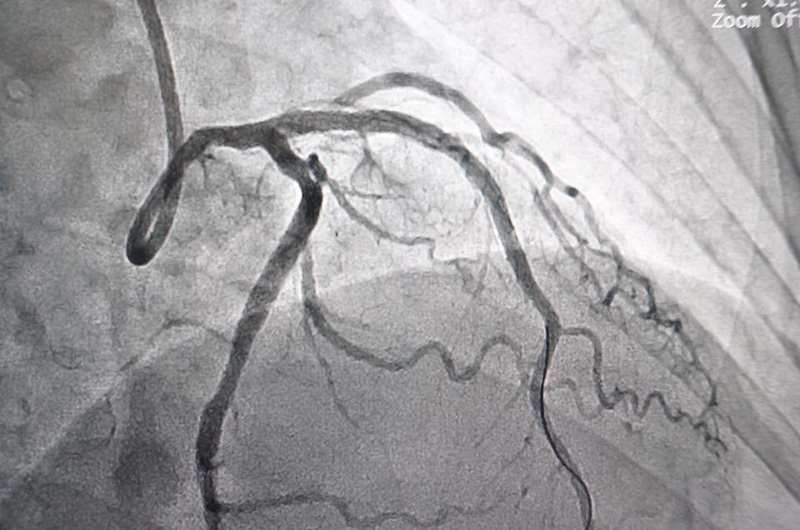

Cơn đau thắt ngực: Cảnh báo bệnh lý tim mạch nguy hiểm Chụp động mạch vành giúp phát hiện động mạch nuôi có bị tắc nghẽn hay không

- Chụp động mạch vành tim: Bác sĩ sẽ đặt một ống mỏng trong mạch máu ở tay hoặc đùi. Sau đó đưa ống này lên tim, bơm thuốc cản quang để quan sát các mạch máu nuôi tim. Phương pháp này sẽ phát hiện động mạch nuôi tim của bạn có bị tắc nghẽn hay không.